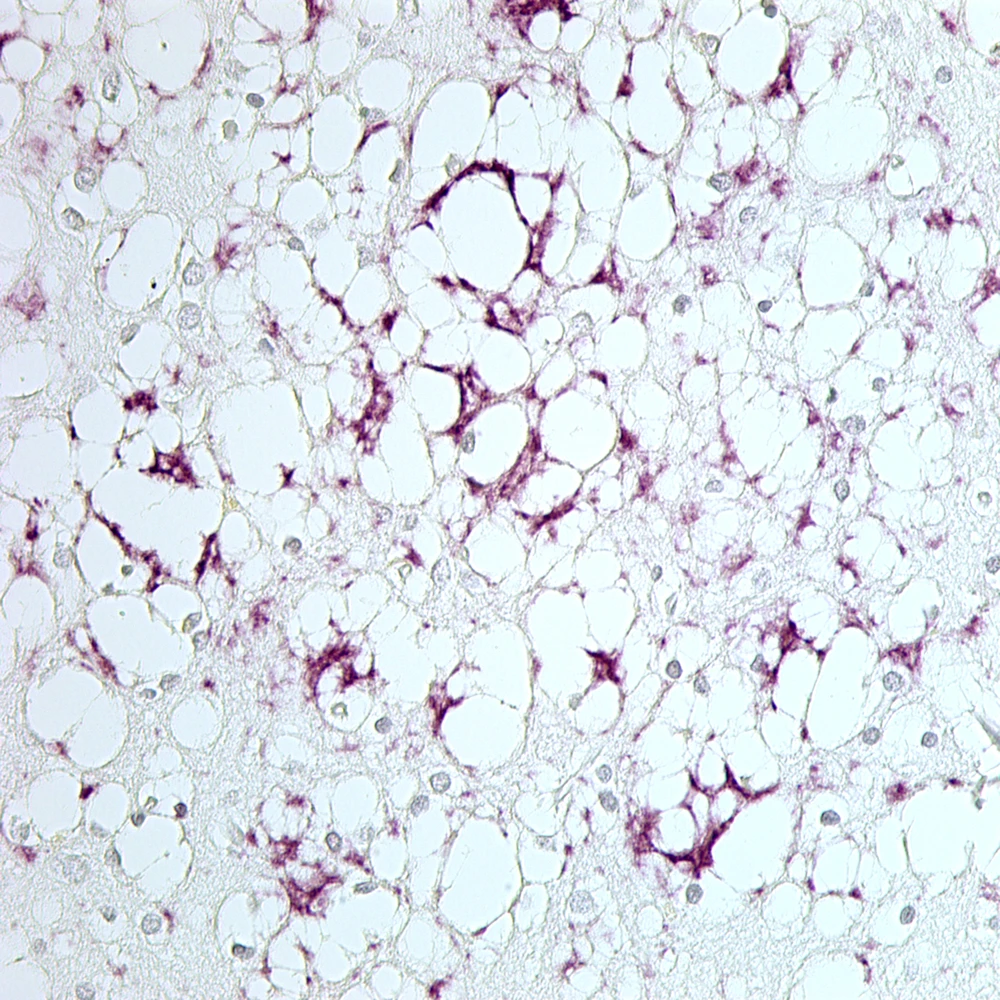

Não bệnh nhân mắc bệnh CJD bị thoái hóa thần kinh và hình thành các mô lớn prion màu tím. (Nguồn: scientificamerican.com)

Prion là nhân tố gây ra các chứng bệnh nguy hiểm ở não như bệnh CJD ở người, bệnh ngứa điên ở cừu và bệnh bò điên ở gia súc.

Prion là một nguyên nhân tuy hiếm nhưng quan trọng của bệnh mất trí nhớ, và giờ đây các nhà khoa học đã nhận diện được tiến trình các prion thay đổi hình dạng và liên kết nhau tạo thành chuỗi polyme gây tổn thương não. Tiến trình này còn được ghi nhận ở các chứng mất trí nhớ thông thường khác như Alzheimer, Parkinson và các bệnh thoái hóa hệ thần kinh khác.